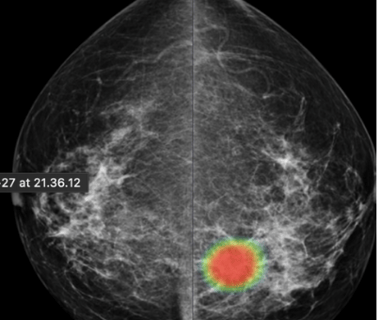

DAM - Breast Solution

To help radiologists improve the predictive accuracy of screening mammography, we present a deep learning method that can detect breast cancer on screening mammograms using a "end-to-end" training technique that efficiently leverages training datasets with either full clinical annotation or merely the cancer status (label) of the entire image. Our training data include biopsy confirmed types of benign or malignant tumors.

Breast cancer detection

Tumor type classification

Breast cancer metastases localization